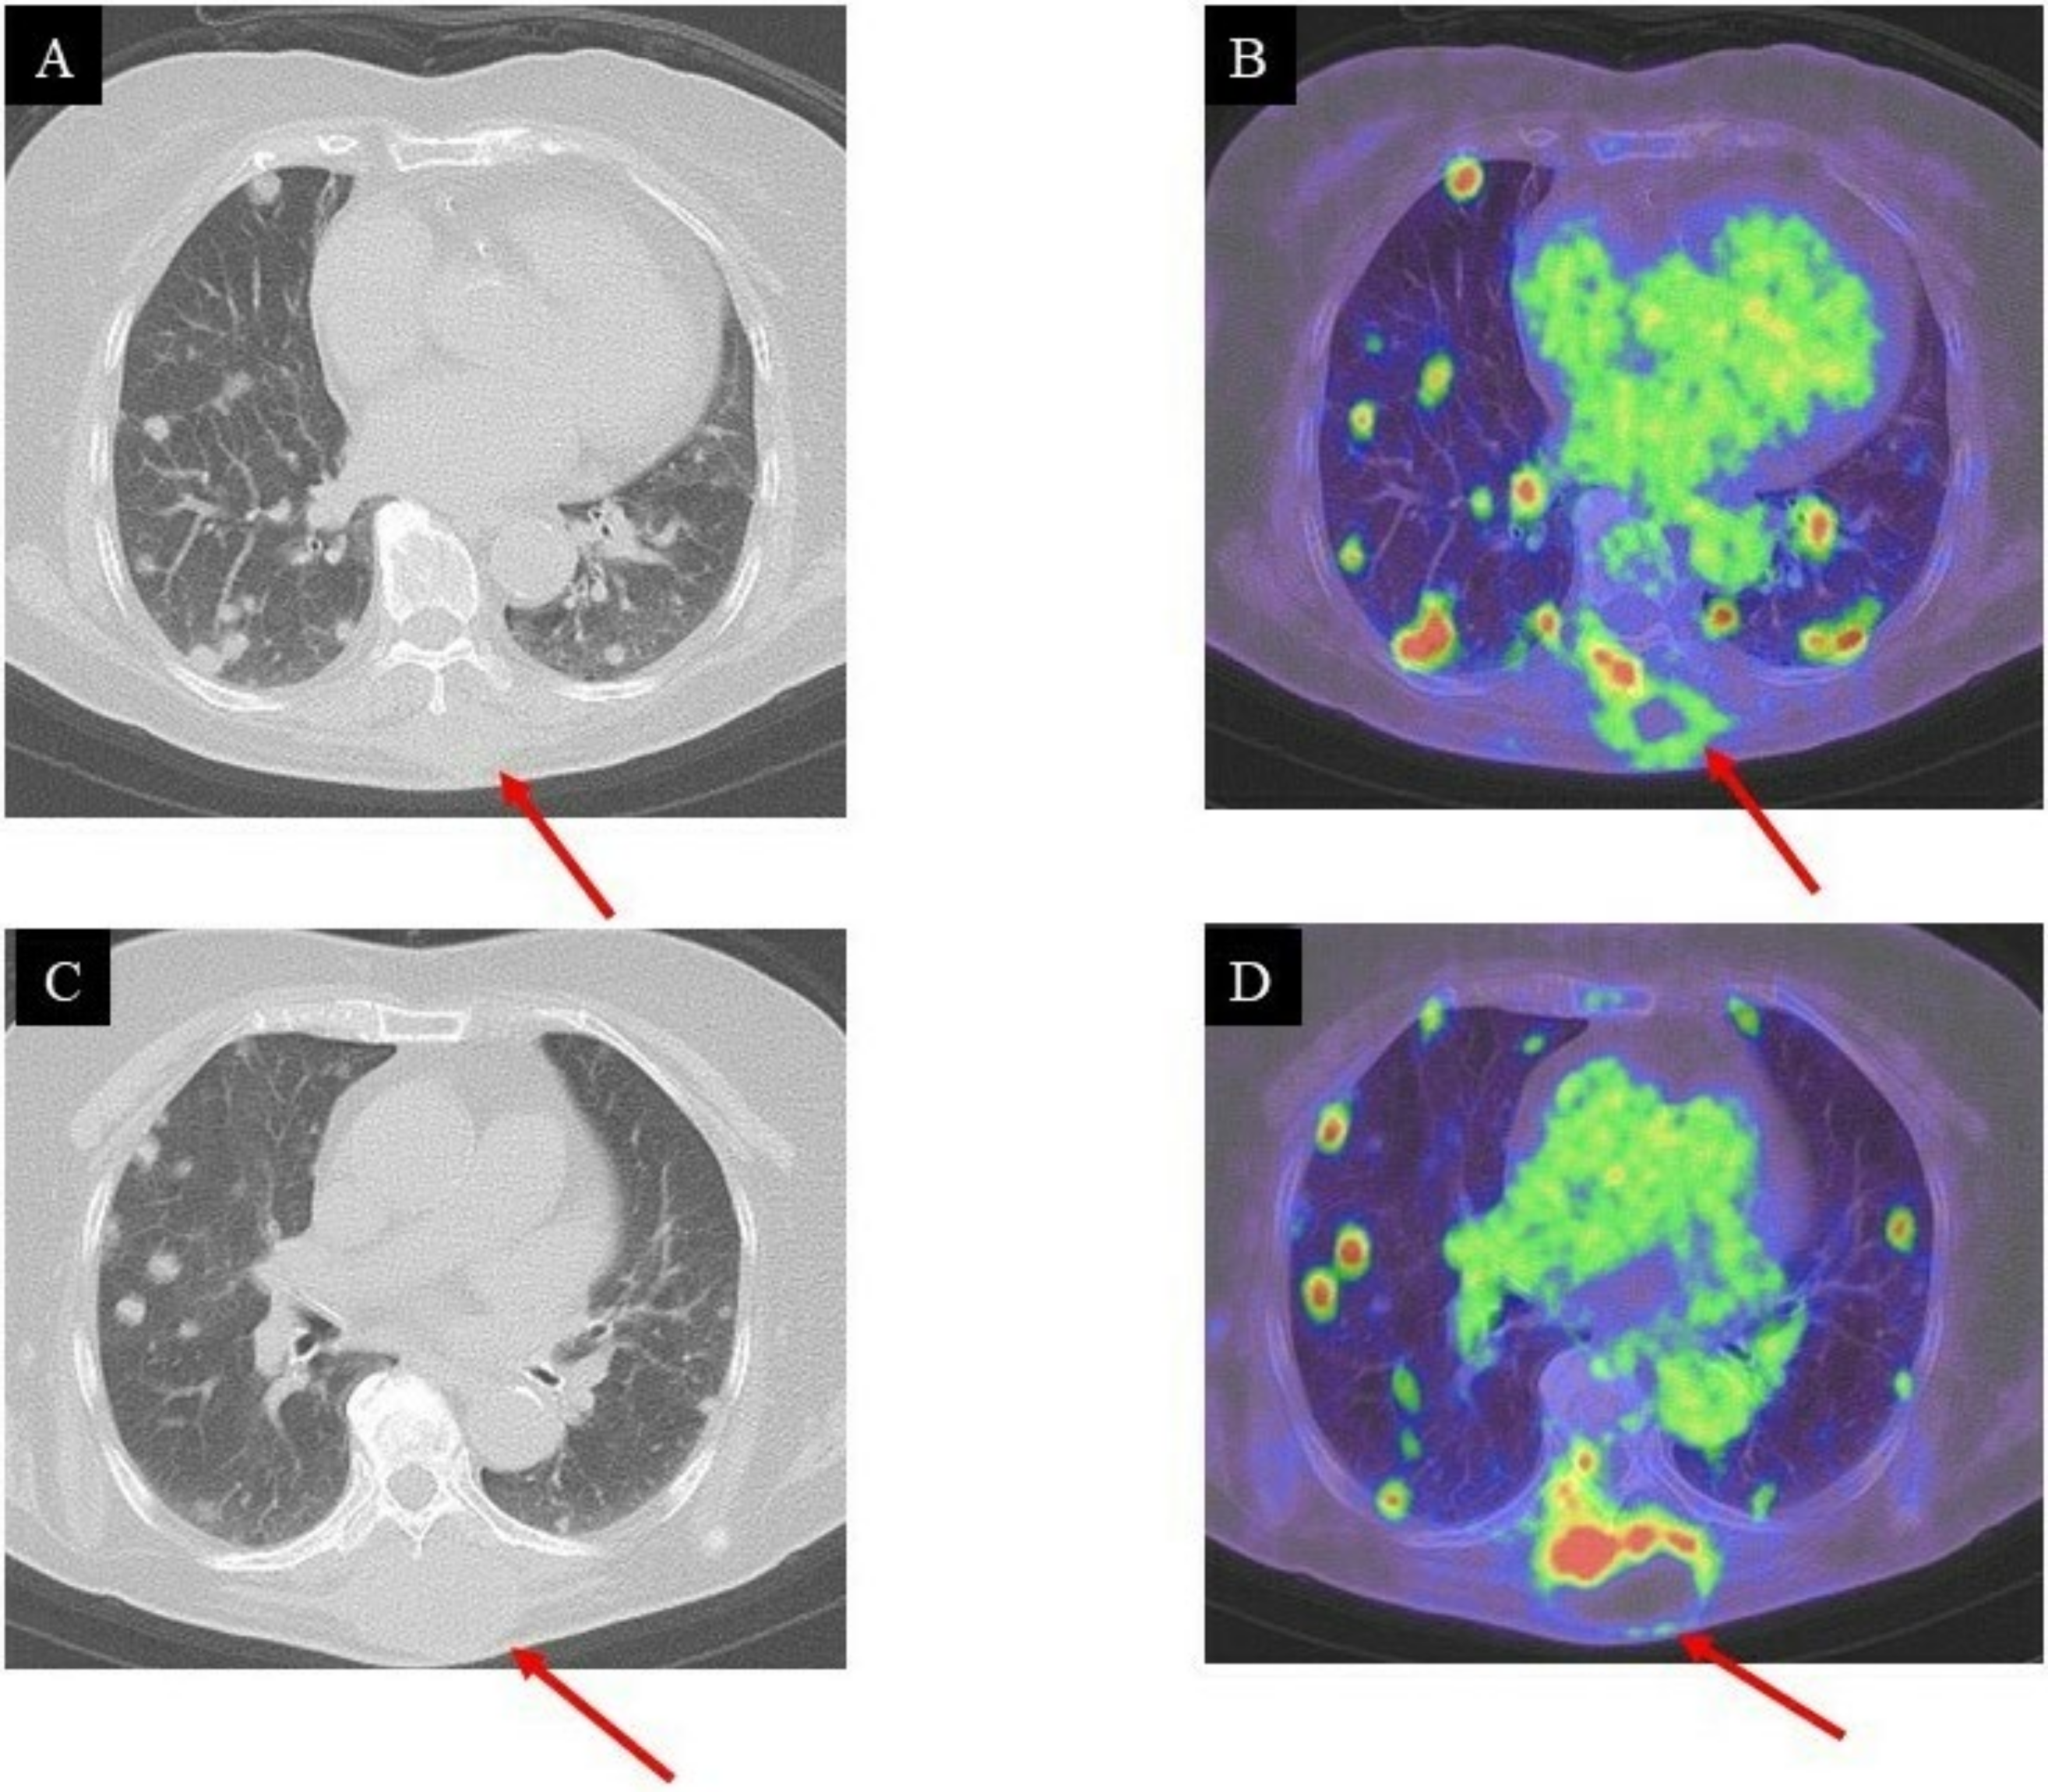

2. Case Presentation